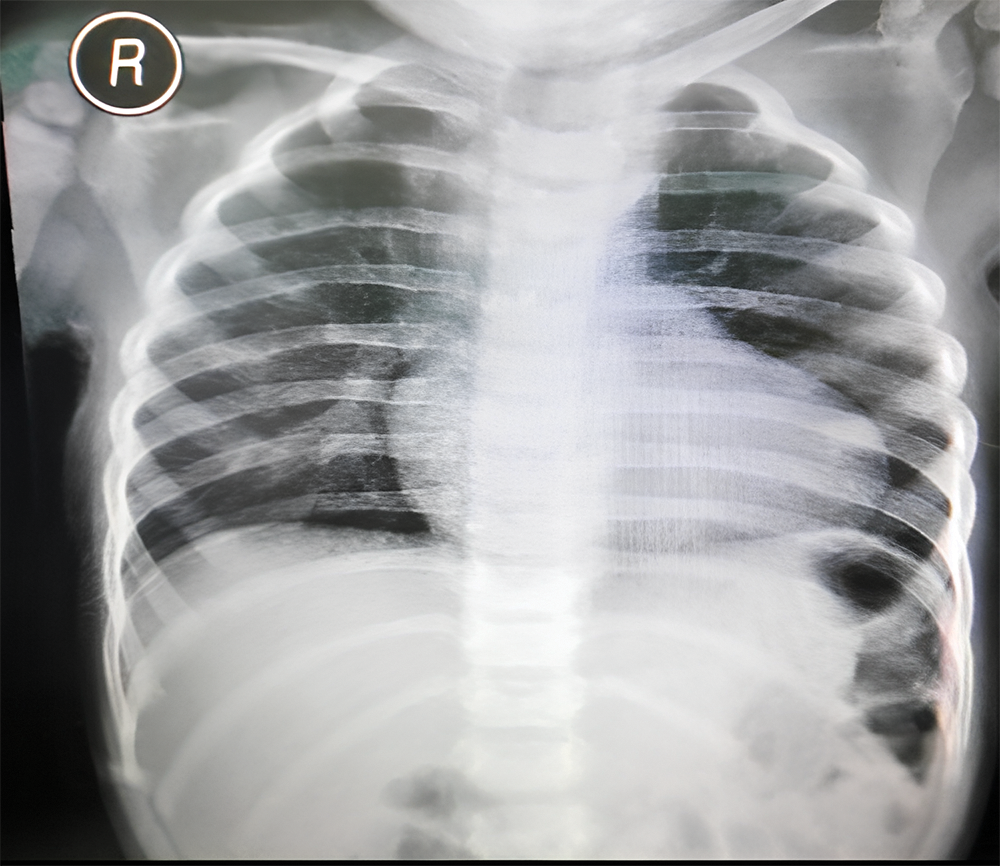

A 2-year-old girl who weighed 10 kg presented with symptoms of dyspnea and cyanosis, which were exacerbated by physical activity. The symptoms were alleviated when the patient was performing a squatting position. During physical examination, blood pressure (BP) was 92/66 mmHg, heart rate (HR) 100 bpm, and room air oxygen saturation (SaO2) varied between 62%–69%. Chest radiograph showed cardiomegaly with cardiothoracic ratio of 55%, flat heart waist with downward apex, and oligemic vasculature appearance (Fig. 1).

Figure 1: Preoperative chest radiograph revealing cardiomegaly with cardiothoracic ratio 55%, normal aortic segment, flat heart waist, downward apex, and oligemic vasculature appearance